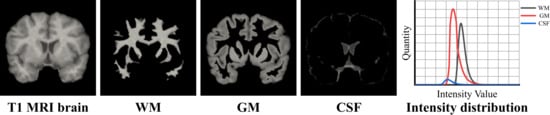

2.2. The Reassignment of the Segmentation Masks

3.2. The Ablation Experiments on Synthetic 2D Data